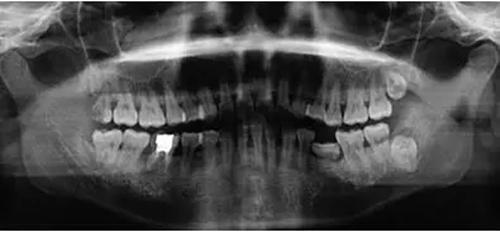

臨床檢查46面見大面積銀汞充填物,近中頰側(cè)部分牙體折裂至齦下約2mm,折裂部分已與牙體分離。46叩痛(-),松動(dòng)度(-),牙齦(-),未探及牙周袋形成。曲面體層片示46髓腔內(nèi)及根管見高密度影像,未至根尖,根尖未見明顯陰影(圖1)。

圖1 拔牙術(shù)前曲面體層片 診斷46折裂牙(死髓牙)。